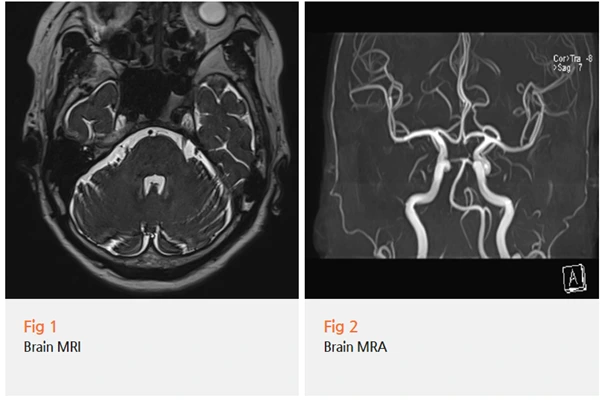

저는 이 환자분께 정확한 원인을 찾기 위해 여러 검사를 진행했어요.

✅ 뇌 MRI: 혈관이 신경을 누르는지 확인

✅ MRA: 혈관의 구조와 위치 파악

✅ 목 엑스레이: 경추의 문제 확인

검사 결과를 보니, 예상했던 대로였어요.

삼차신경을 혈관이 직접적으로

누르고 있는 전형적인 모습은 아니었어요.

대신 목에 문제가 있었죠.

경추부, 그러니까 목뼈 부분에 구조적인 문제가 있었고,

이게 삼차신경통을 악화시키고 있었던 거예요.